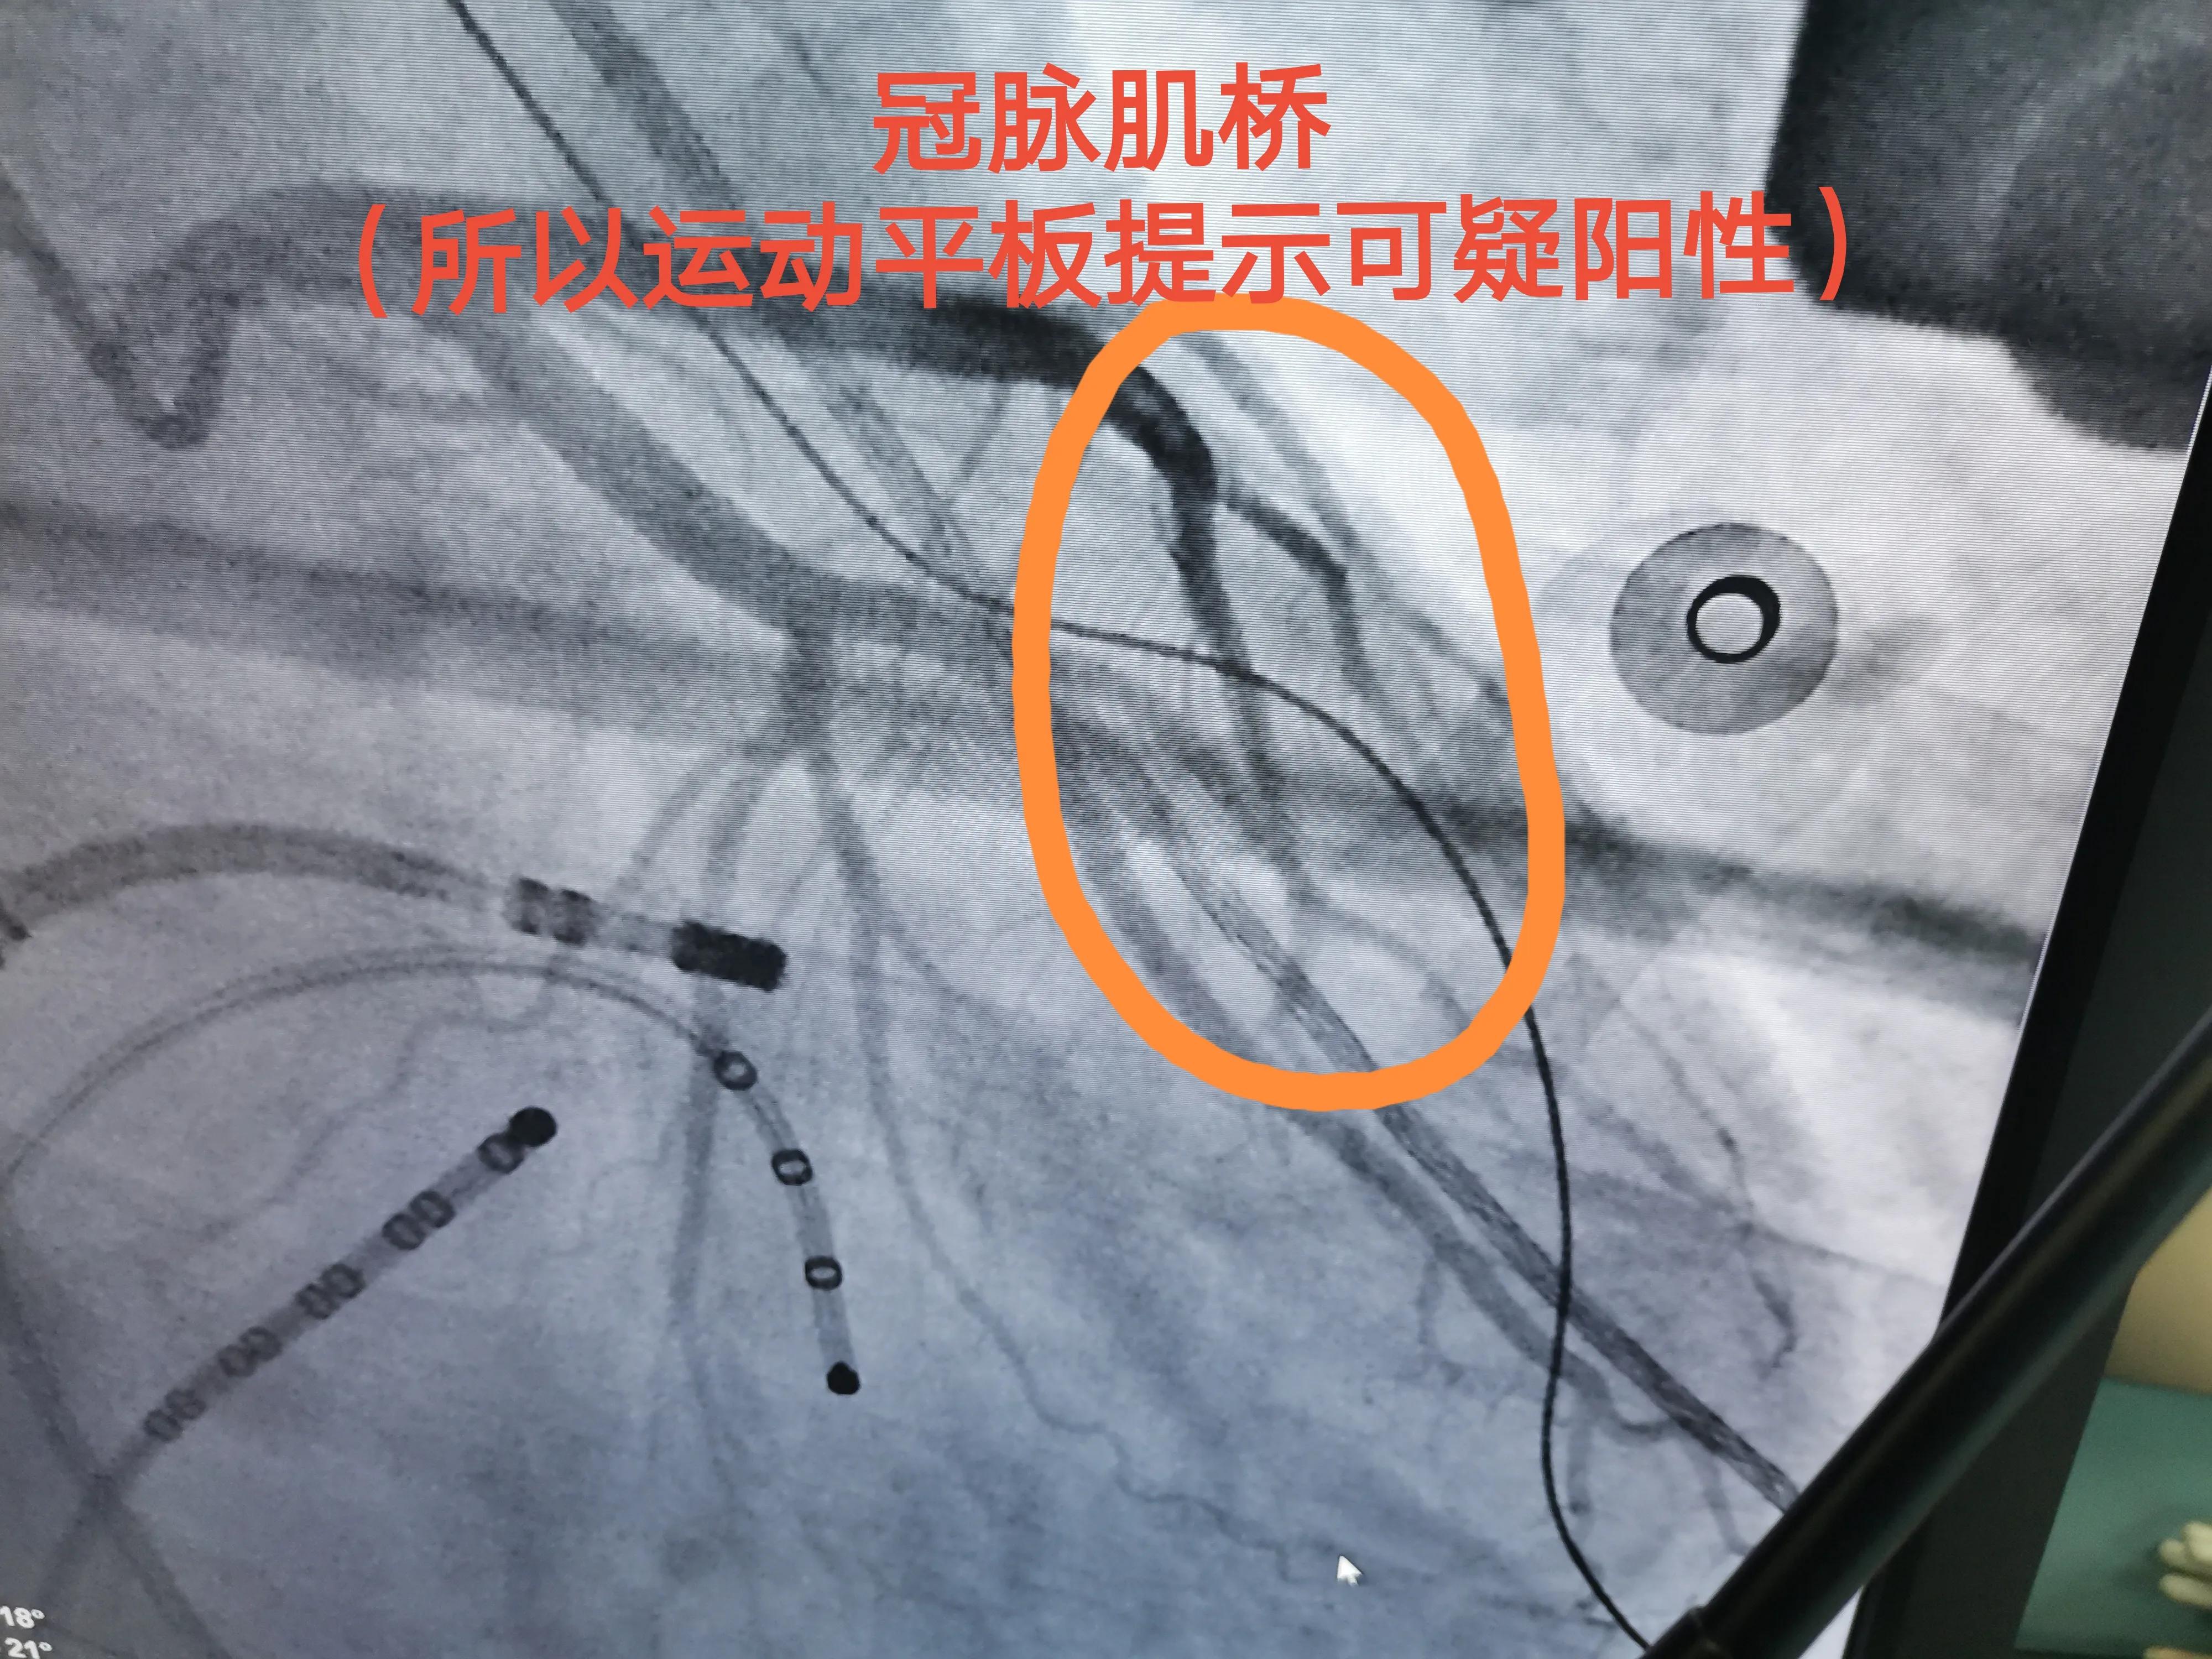

观察期间做了造影,病人没有什么冠心病危险因素,运动平板阳性,果然是“冠脉肌桥”引起的,放心了!